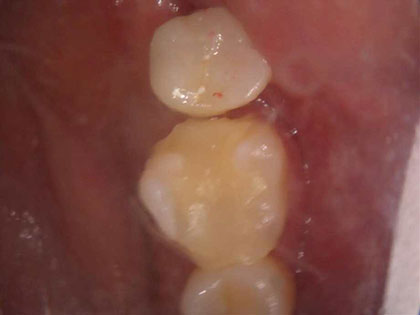

• 初診時の写真がこちら

• インプラント術前1